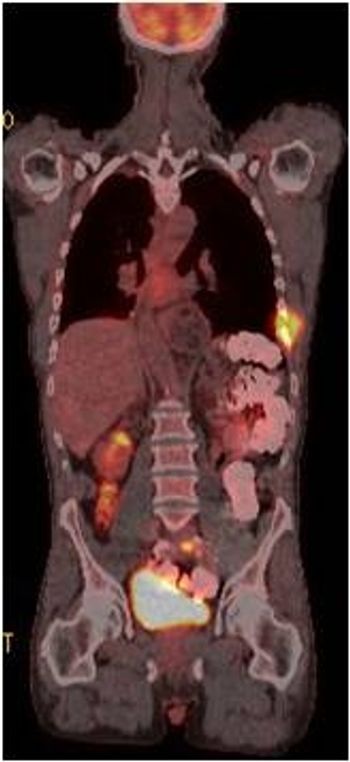

Plans for the 2009 SNM meeting in Toronto demonstrate the growing numbers and widening world of molecular imaging science and practice. Organizers expect nearly 4000 attendees drawn to 600 oral presentations and 1000 poster presentations covering everything from the basic chemistry of radiopharmaceutical design to growing evidence that FDG-PET/CT can indicate whether cancer therapies are working.

Imagine an exam that combines into a single scan the diagnostic imaging power of 10 PET studies, each measuring an essential dimension of cancer's aggressiveness, metastatic potential, and susceptibility to radio- and chemotherapy.